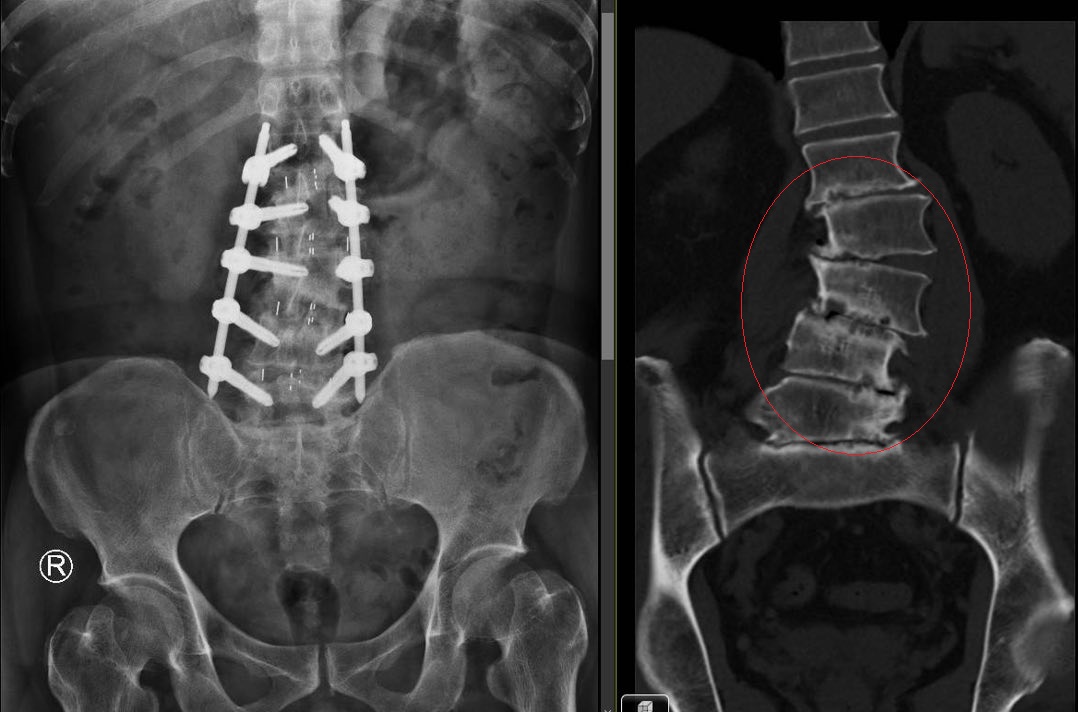

圖說:胡先生第1至第5節腰椎的椎間盤嚴重磨損退化(右)側彎嚴重,經OLIF手術後影像(左)已扶直。

部彰醫師陳柏辰表示,經影像檢查發現,胡先生第1至第5節腰椎的椎間盤已嚴重磨損退化,磨到扁平,導致脊椎側彎與滑脫,這正是長年背痛、無法多走路的病灶根源。傳統脊椎手術通常採「後背進入」,患者必須趴著,醫師需小心翼翼閃避密集的脊神經才能觸及患部。而新式脊椎微創手術(OLIF),則是讓患者側躺,從腰側的肌肉自然縫隙進入脊椎,不需破壞大片骨骼與肌肉,出血量極少,安全性高,有效避開危險神經區域,降低神經損傷風險,也因為傷口小,術後疼痛感大幅降低,病患能迅速回歸日常。

陳柏辰醫師指出,他為胡先生進行新式脊椎微創手術(OLIF),除了清除受損的椎間盤,並植入高分子聚合物的「斜位融合支架」,支撐力是傳統支架的3至5倍,穩固地將萎縮的椎間盤空間撐開,再配合骨釘植入,成功矯治了胡先生的脊椎側彎。